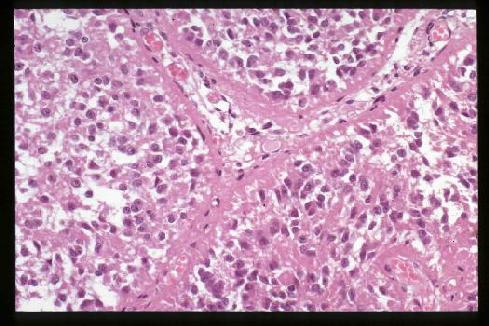

1. Light microscopic features of the human pinealocytes

Human pinealocytes

Human pinealocytes in alveolar arrangement (H&E stain). The appearance

of the pineal gland is fairly different even within the mammalian,

not to mention the dramatic morphological changes in the process of the evolution of

vertebrates from fish to human. The phylogenesis of the pineal may be more

interesting than Much Melatonin About Nothing.